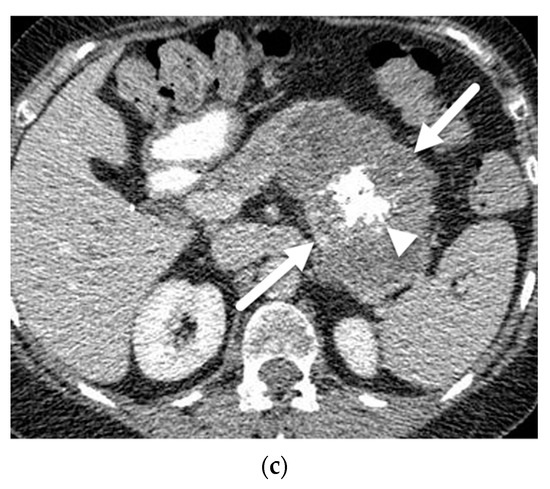

- Cantisani, V.; Mortele, K.J.; Levy, A.; Glickman, J.N.; Ricci, P.; Passariello, R.; Ros, P.R.; Silverman, S.G. MR imaging features of solid pseudopapillary tumor of the pancreas in adult and pediatric patients. AJR Am. J. Roentgenol. 2003, 181, 395–401. [Google Scholar] [CrossRef]

- Yu, M.H.; Lee, J.Y.; Kim, M.A.; Kim, S.H.; Lee, J.M.; Han, J.K.; Choi, B.I. MR imaging features of small solid pseudopapillary tumors: Retrospective differentiation from other small solid pancreatic tumors. AJR Am. J. Roentgenol. 2010, 195, 1324–1332. [Google Scholar] [CrossRef]